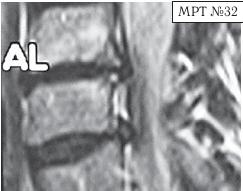

Так продолжалось практически год, пока не появилась боль в левой руке и онемение IV и V пальцев. Занятия на тренажёре только усиливали боли, а лекарства практически не действовали. В связи с чем он был вынужден опять обратиться в ту же клинику. После лечения (практически по той же схеме) боли уменьшились, но полностью не прошли, онемение усилилось. Через некоторое время появилась субфебрильная температура (37–37,2 °C), общая слабость, частые головные боли, головокружения. По жалобам и ощущениям с его слов: «На голову надели будто тесную шапку и она сдавливает. А в голове туманность какая-то, мысли путаются, на чём-то сосредоточиться практически невозможно. Порой забываю, что минуту назад делал. Такое ощущение, что в голове полно посторонних мыслей: только от одних отделаюсь, как появляются другие» и так далее. Естественно, он вынужден был опять обратиться в медицинское учреждение, где ему повторно сделали МРТ (№ 32).

После обследования у него было обнаружено:

— абсолютный стеноз спинномозгового канала шейного отдела позвоночника с полным блоком ликворных путей и сдавлением дурального мешка спинного мозга на уровне сегментов CV-CVI и CVI-CVII;

— в сегменте CV-CVI — значительный спондилёз, гипертрофия задней продольной связки, и практически компенсированная спондилёзом грыжа межпозвонкового диска;

— в сегменте CVI-CVII — довольно активная грыжа межпозвонкового диска;

— на уровне поражённых сегментов выраженный эпидурит.

После данного обследования, когда врачи увидели грыжи межпозвонковых дисков, да и то, что происходило у пациента в шейном отделе позвоночника, они стали категорически настаивать на немедленной операции. Однако перспектива стать инвалидом на всю оставшуюся жизнь явно не прослеживалась в планах пациента. Когда прозвучали два слова — «грыжи» и «операция», этот человек, естественно, тут же вспомнил и про меня, и про нашу давнишнюю с ним дружбу.